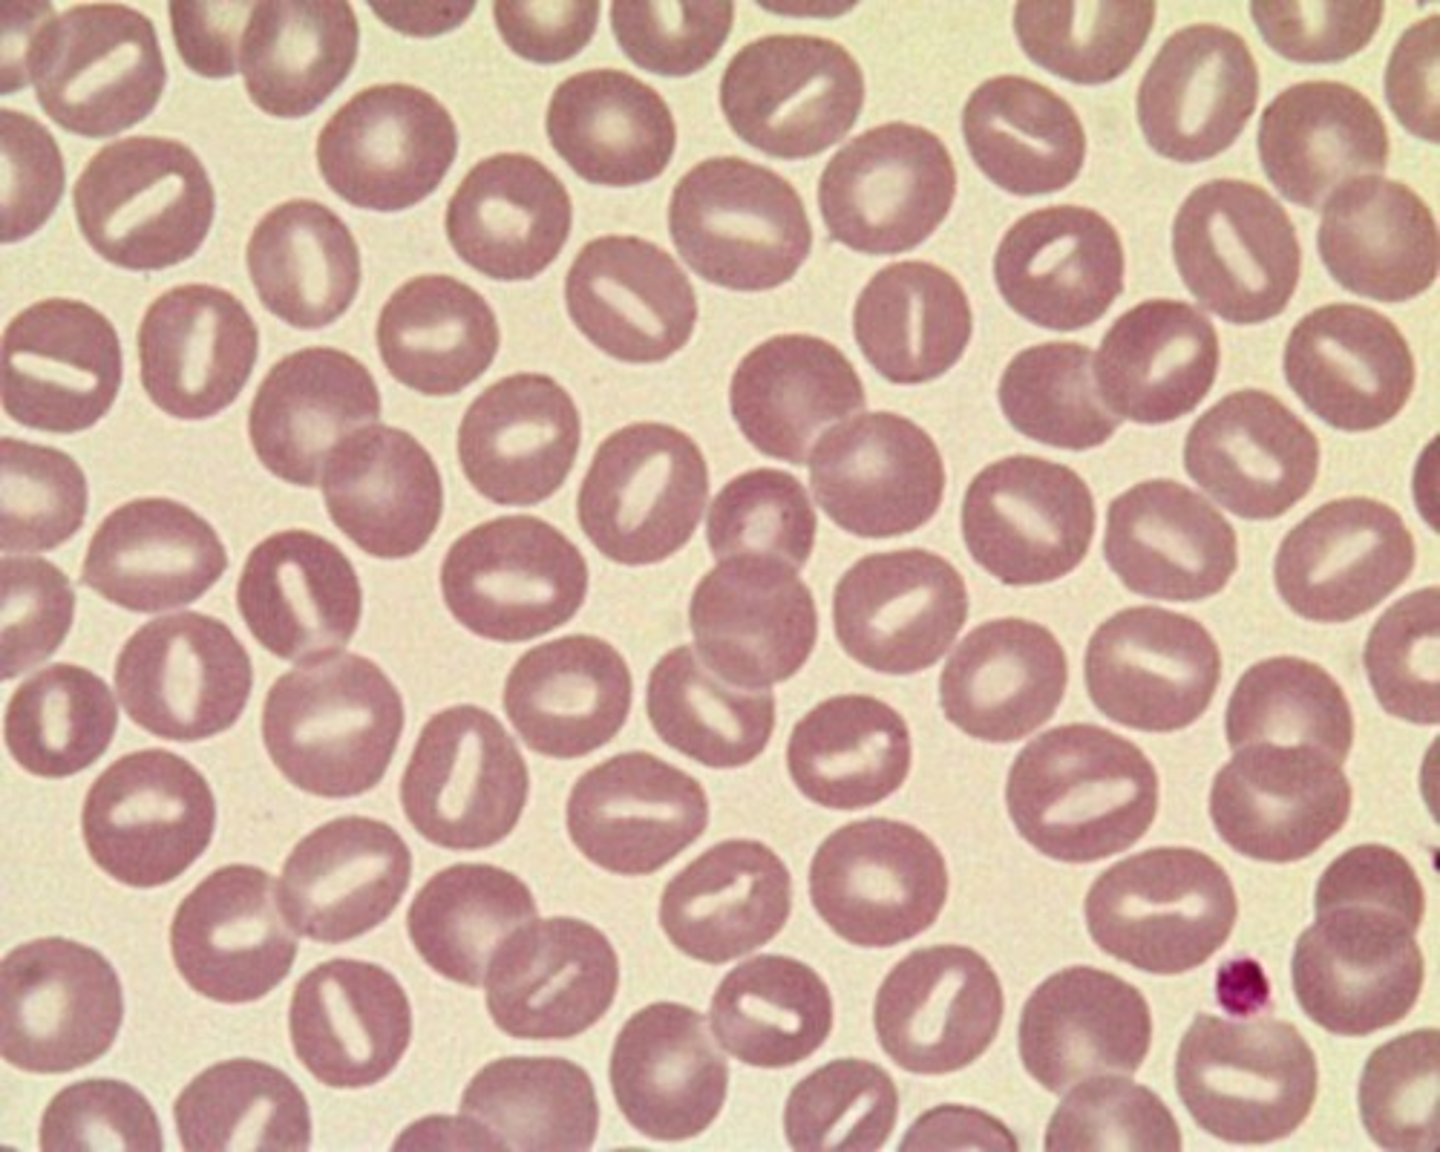

ovalocytes/elliptocytes

oval in shape

elliptical shaped

-spiculated with evenly spaced, uniform projections